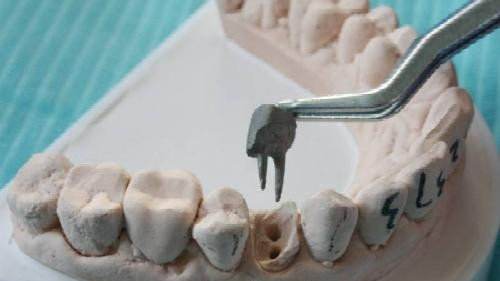

3、確定根管工作長(zhǎng)度:應(yīng)用平行投照X線方法、根管長(zhǎng)度測(cè)量?jī)x確定根管度,好插針拍X片。

4、根管預(yù)備:根管清理成形的目的是去凈根管壁上的感染物,通過根管器械的切削作用去除感染的牙本質(zhì)并清理根管壁細(xì)菌以利于根管充填。

7、根管打樁:因牙體缺損過多,導(dǎo)致牙的強(qiáng)度(承受力量的性能)大幅度下降,不能很好地承受咀嚼力量。打樁的目的是增加牙根及牙冠的強(qiáng)度,增加患牙的穩(wěn)固。